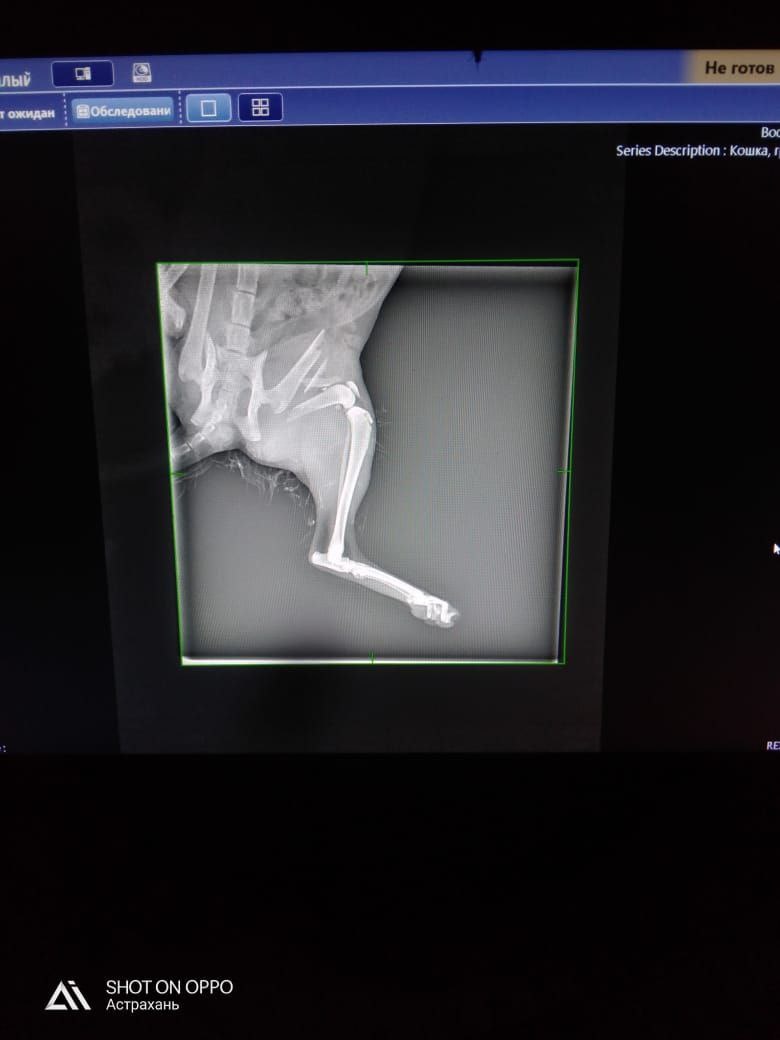

Просим оказать помощь в сборе средств на лечение молоденькой кошечки, которую погрыз домашний соседский пес.

Требуется операция на лапу, уже затрачено 17 100.